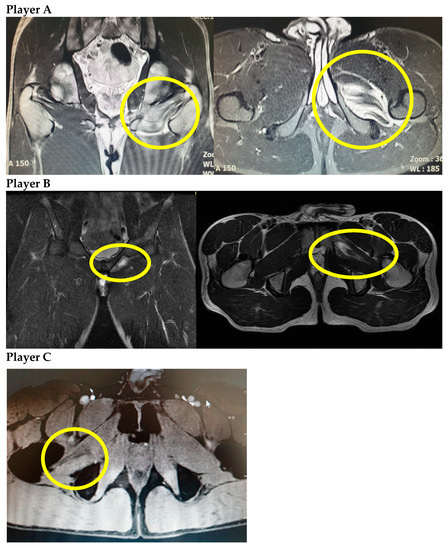

Acute Obturator Externus Injury in Professional Soccer Players: A Case Series

2. Presentation of Cases